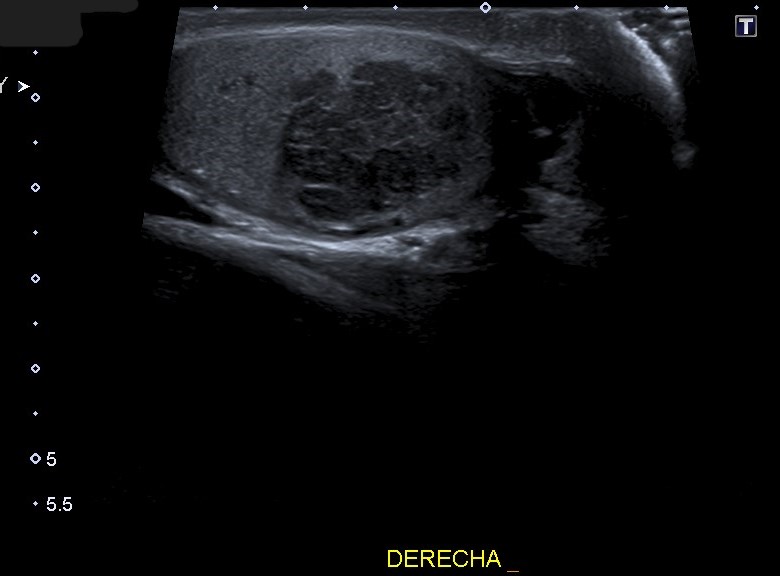

Ecografía escrotal: En testículo derecho se aprecia lesión heterogénea de predominio hipoecogénico con alguna calcificación grosera, polilobulada, de bordes mal definidos, con medidas aproximadas de 36 mm de diámetro máximo, con vascularización en su interior en el registro Doppler, sugestivo de proceso neoformativo testicular. No se objetiva engrosamiento epididimario ni de cubiertas escrotales.